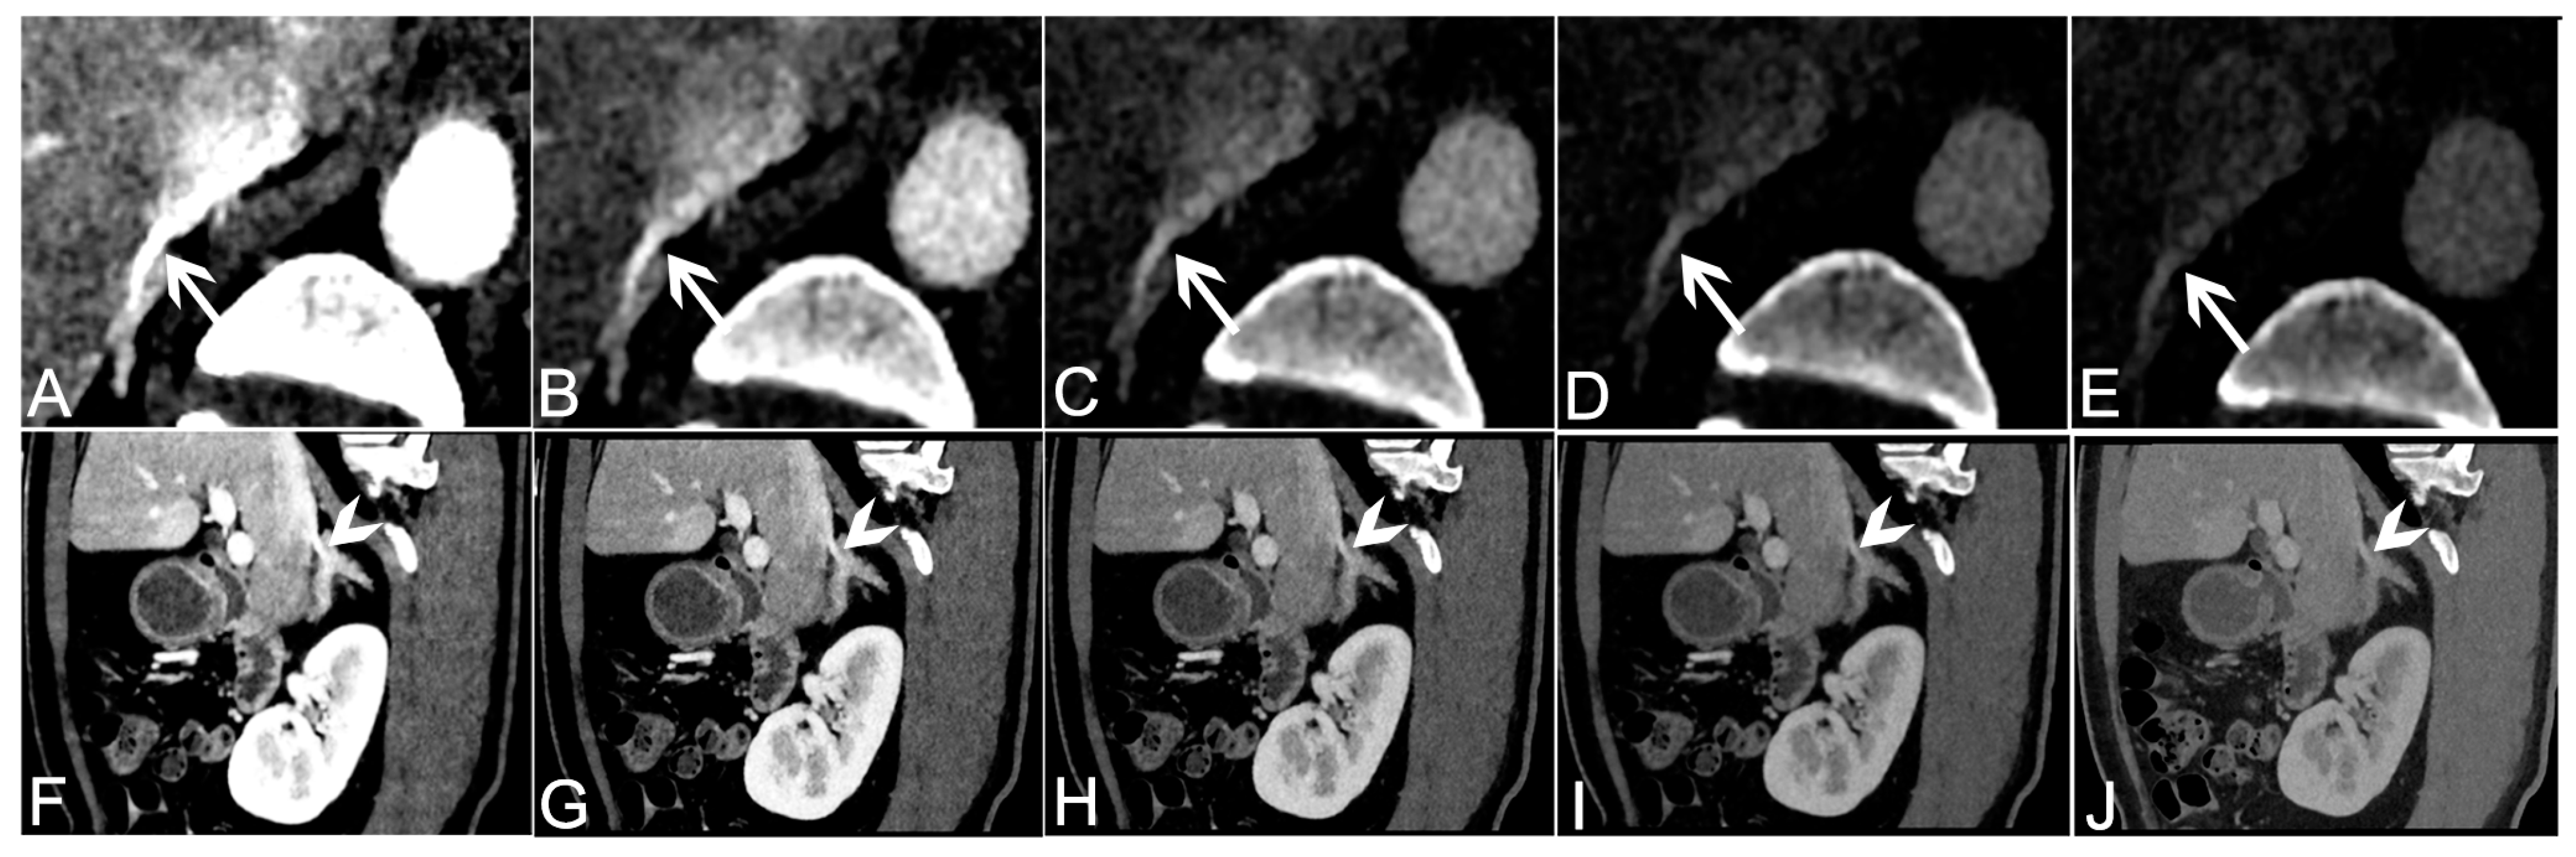

| 40 keV VMI+ | 50 keV VMI+ | 60 keV VMI+ | 70 keV VMI+ | 80 keV VMI+ | |

|---|---|---|---|---|---|

| Right Adrenal Vein | |||||

| 4 (excellent) | 26 | 3 | 3 | 0 | 0 |

| 3 (good) | 13 | 31 | 15 | 4 | 0 |

| 2 (fair) | 0 | 5 | 21 | 6 | 7 |

| 1 (poor) | 0 | 0 | 0 | 29 | 32 |

| detectability | 100% (39/39) | 87.18% (34/39) | 46.15% (18/39) | 10.26% (4/39) | 0% (0/39) |

| score | 4 (4,4) | 3 (3,3) | 2 (2,3) | 2 (2,2) | 1 (1,1) |

| p | <0.01 * | <0.001 * | <0.001 * | <0.001 * | |

| kappa | 0.80 | 0.86 | 0.86 | 0.73 | 0.80 |

| Left adrenal vein | |||||

| 4 (excellent) | 24 | 7 | 0 | 0 | 0 |

| 3 (good) | 14 | 30 | 25 | 10 | 0 |

| 2 (fair) | 1 | 2 | 14 | 26 | 20 |

| 1 (poor) | 0 | 0 | 0 | 3 | 19 |

| detectability | 97.44% (38/39) | 94.87% (37/39) | 64.11% (25/39) | 25.64% (10/39) | 0% (0/39) |

| score | 4 (4,4) | 3 (3,3) | 3 (2,3) | 2 (2,3) | 2 (1,2) |

| p | 0.008 * | <0.001 * | <0.001 * | <0.001 * | |

| kappa | 0.79 | 0.87 | 0.89 | 0.78 | 0.89 |